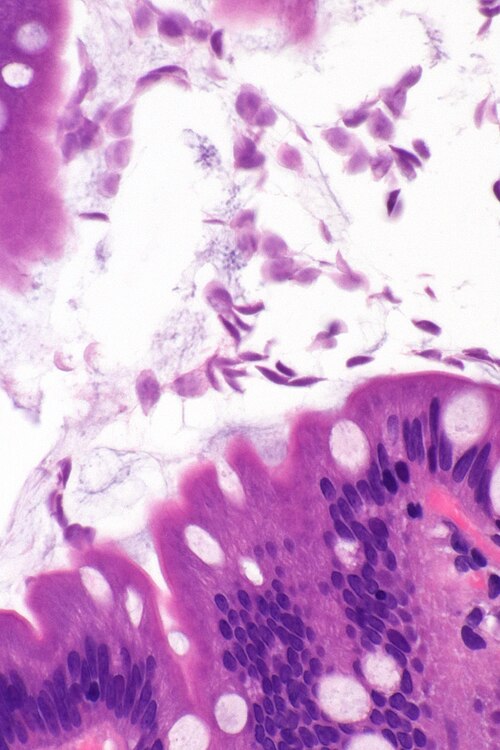

Very high magnification

Very high magnification. H&E stain.